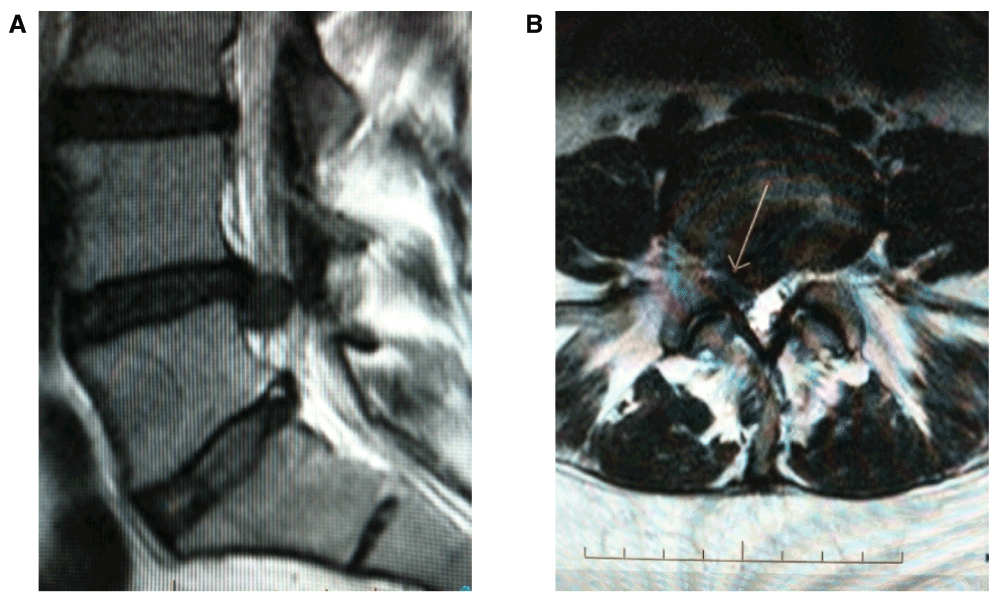

Figure 1 from Efficacy of Intradiscal Ozone Therapy with or without Herniated Disc Ozone Therapy Ozone therapy works to decrease the pain within the lumbosacral joint by dehydration. Lumbar disc herniation (ldh) is a common cause of low back pain (lbp). Ozone therapy as a treatment for low back pain secondary to herniated disc: Recently, in the setting of lbp caused by ldh, a. Several therapeutic mechanisms have been proposed for intradiscal ozone injections for. Herniated Disc Ozone Therapy.